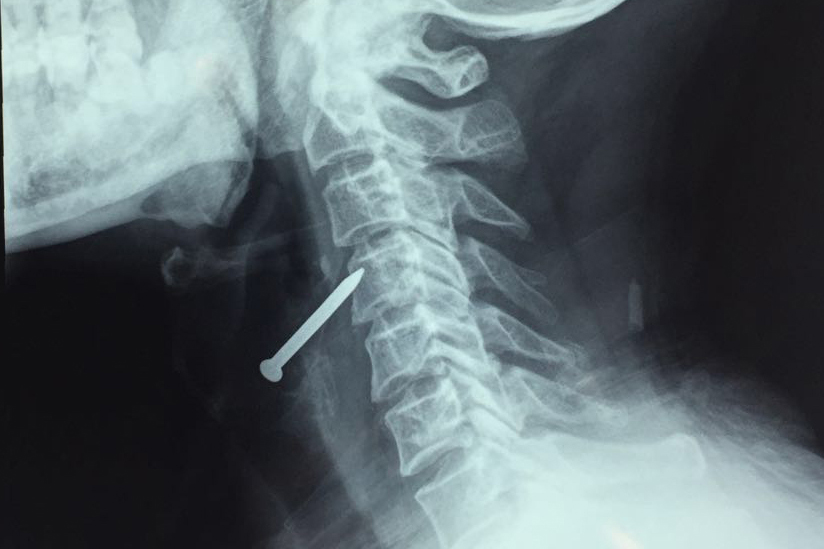

我院耳鼻喉科近日接诊了一位铁钉误伤颈部的患者,并为其及时手术,得以化险为夷。

据悉,患者在工作中,一枚铁钉误伤到了他的颈部,受伤后感觉颈部痛疼不适,没有明显的呼吸困难、吞咽困难。CT检查显示:右侧颈部软组织见钉状金属密度影,内长3.2cm,周围软组织略肿胀,未见出血密度影,异物位于环状软骨上方,与颈内动静脉毗邻,未伤及气管及食道。耳鼻喉科副主任医师李臻表示,“时间就是生命,及时取出异物对于患者的生命及预后起着至关重要的作用。这个时候如果不及时取出异物,随时都有刺破颈部大血管导致死亡的可能。”

耳鼻喉科立即通知手术室进行急诊手术,完善检查后,吕超、李臻两位大夫在局麻下为患者取出铁钉,术中小心分离软组织,随时预防出现大出血的可能,整台手术顺利完成。